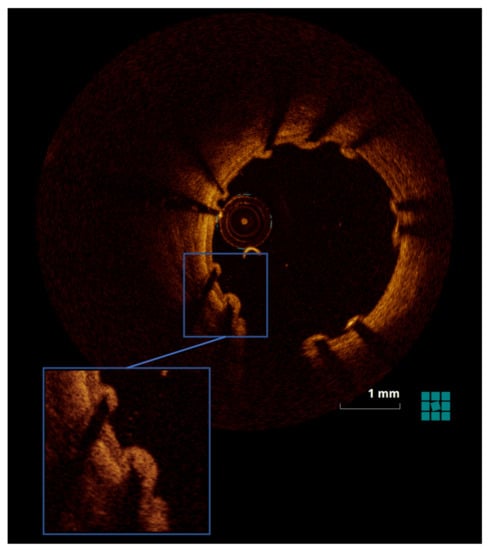

2.4.2. OCT

3.1.2. OCT